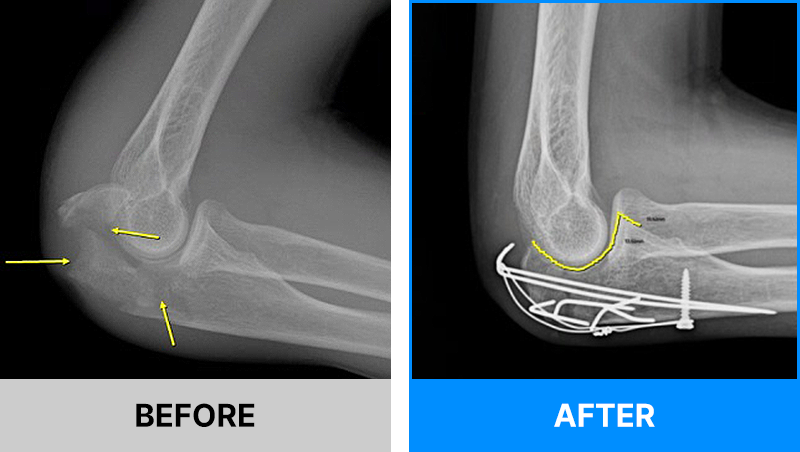

왜 당일 입퇴원 수술일까요?

오래 입원할 필요가 없기 때문입니다.

서울거탑정형외과에서는 전신마취, 척추마취가 아닌

국소부분마취(신경차단) 및 수면 마취를 통해 수술을 시행합니다.

수술 가능 여부 확인은 대표원장과의 진료가 필요합니다.